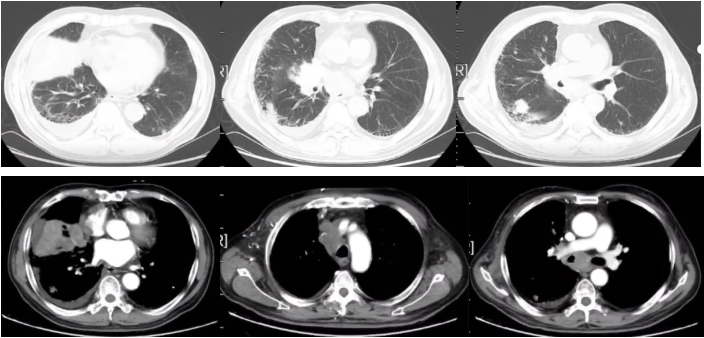

图3

2022-09-17胸部平扫CT:恶性肿瘤维持性化学治疗后,较2022-7-20胸部CT旧片,右肺中叶占位(7.3×4.4cm)缩小;双肺部分结节增大;纵隔及右肺门淋巴结缩小;主动脉左侧旁(2-22)淋巴结稍增大:右侧胸腔积液增多;左侧新增胸腔积液;胸壁水肿增厚,双侧腋窝小淋巴结,请结合临床;余未见显著变化。附见,胰尾较前稍增粗:肝S4段新增低密度小结节,请结合腹部相关检查。

疗效评价:SD。

2022-11-16胸部平扫CT:恶性肿瘤维持性化学治疗后,较2022-9-16日胸部CT,右肺中叶占位(2.2×1.9cm)缩小;双肺大部分结节消失;右侧胸腔积液减少,左侧胸腔积液消失;纵膈及双侧腋窝淋巴结缩小;扫描层面内肝脏结节本次未见明确显示,胰腺结节缩小;余较前变化不大。

疗效评价:PR。